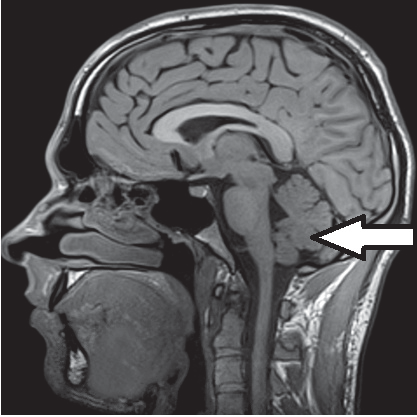

Na obrazie rezonansu magnetycznego strzałką oznaczono wyrostek kolczysty kręgu

Ilustracja do pytania 27

A. szyjnego w płaszczyźnie strzałkowej.

B. szyjnego w płaszczyźnie czołowej.

C. piersiowego w płaszczyźnie czołowej.

D. piersiowego w płaszczyźnie strzałkowej.